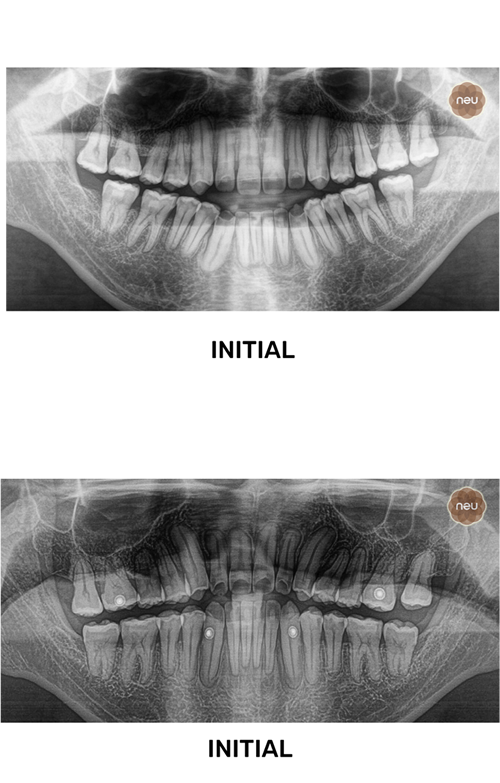

THE CHALLENGE

Usually, a reversed bite affects looks and function.

But at Neu, we correct it with precise, customized treatment.

Usually, long-untreated cases are harder to fix.

But at Neu, we create a careful step-by-step plan to restore both function and aesthetics.

Usually, complex bite corrections take time.

But at Neu, we use digital planning and bite simulations to guide each step with precision.